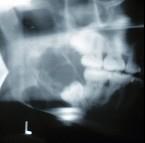

问题 某患者一侧下颌磨牙区、下颌角及升支部渐进性膨大,按之有乒乓球感。X线片(如图)示多房性密度减低影,分房大小相差悬珠,分隔清晰锐利、阴影边缘呈切迹状,阴影内牙根尖有不规则吸收。该病最可能的诊断是()

选项 A.成釉细胞瘤 B.牙源性角化囊肿 C.牙源性纤维瘤 D.成骨肉瘤 E.颌骨血管瘤

答案 A